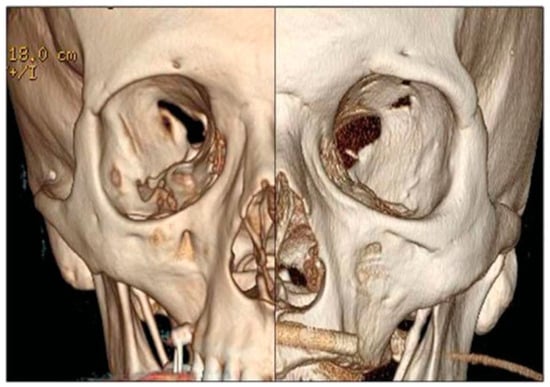

The postsurgical CT scan revealed a full recovery of the right SOF size (Figure 4). One week postoperatively, physical examination showed a great improvement of all symptoms, a prompt and almost complete recovery of the abducens movement, without diplopia (Figure 1). In 1 month, the patient completely healed.

Figure 4. Left: Axial and coronal preoperative CT scan: note SOF size reduction; right: Axial and coronal postoperative CT scan: note SOF size recovery. CT, computed tomography; SOF, superior orbital fissure.